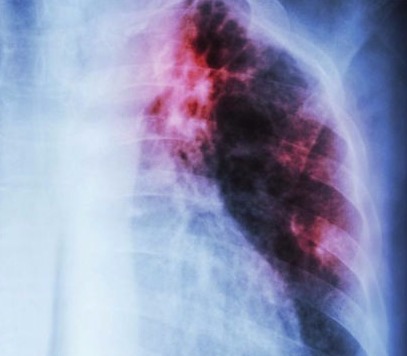

Pneumonia

A Pneumonia é uma inflamação dos pulmões relacionada a um agente infeccioso. Pode ser de origem viral, bacteriana ou fúngica, e o tratamento precoce é o método mais eficaz para a boa evolução do quadro. Se você tem tosse, expectoração, falta de ar, dor no peito, febre, calafrios, perda de peso, não adie sua consulta.